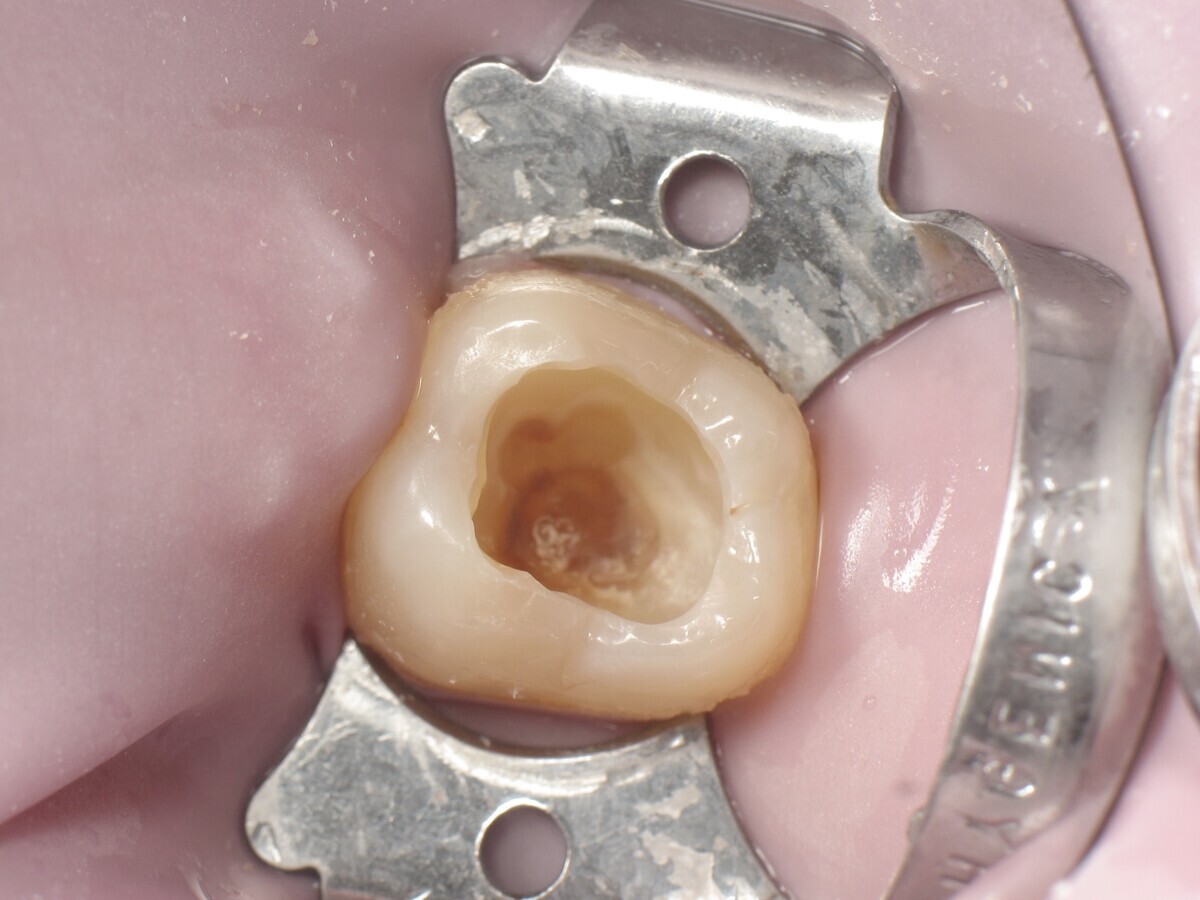

Este artículo describe el tratamiento de una cavidad clase I en un molar utilizando un composite termoviscoso mediante la técnica de la almohadilla (Figura 1). En primer lugar, se registran los detalles anatómicos utilizando una resina transparente, fluida y fotopolimerizable (Clip Flow, VOCO). El diente se aísla con un dique antes de aplicar el composite transparente a la superficie oclusal con un cepillo aplicador y fotopolimerizar durante 10 segundos (Figuras 2-4). La almohadilla oclusal así obtenida (Figura 5) debe almacenarse en alcohol (etanol o isopropanol) para eliminar la capa de inhibición. Luego se limpia la cavidad clase I (Figuras 6 y 7). A continuación se graba el esmalte durante 30 segundos y la dentina durante 15 segundos (Conditioner 36, Dentsply Sirona) y luego se enjuaga bien (Figuras 8 a 10). Debido al bajo espesor de la dentina remanente, también se aplica protección pulpar (Telio Desensitizer, Ivoclar Vivadent) (Figura 11). Luego se frota el adhesivo sobre las superficies dentales durante 20 segundos (Futurabond DC, VOCO), luego se seca bajo una pulverización de aire sin aceite graso durante 5 segundos y luego se fotopolimeriza durante 10 segundos (Figuras 12, 13). Para una humectación óptima, el fondo de la cavidad se cubre con un compuesto fluido de baja viscosidad (GrandioSO Light Flow, A3.5, VOCO) y se fotopolimeriza durante 20 segundos (Figuras 14, 15). Utilizando el Dispensador VisCalor, un dispensador portátil que permite el calentamiento y la aplicación simultánea de resinas, la cavidad se llena luego con un composite termoviscoso bulk (VisCalor Bulk, A2, VOCO).

Figura 01. Molar con caries clase I.

Figura 06. Cavidad durante la excavación.

Figura 07. Cavidad después de la excavación.